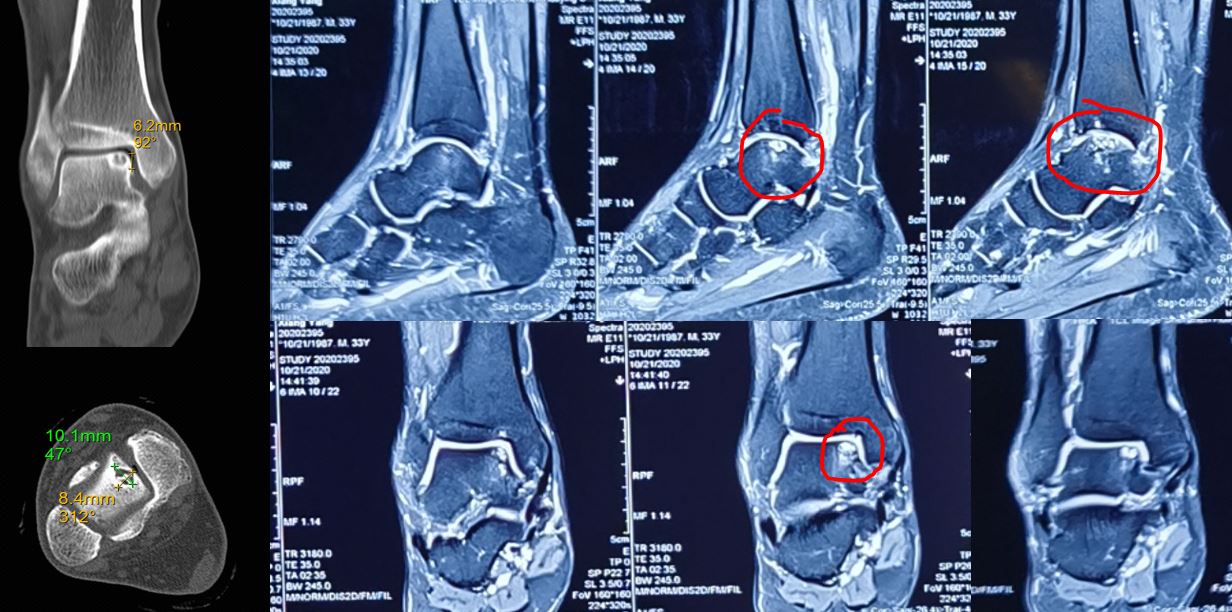

距骨骨软骨损伤(talarosteochondral lesions,t0CLs)是引起踝关节疼痛和残疾的常见疾病之一,患者大部分有明确的踝关节外伤史,严重者可致踝关节不可纠正的畸形。根据软骨损伤区域、位置及是否合并骨髓水肿和软骨下囊肿,距骨骨软骨损伤治疗方法包括微创手术和骨软骨移植等修复方法。

(核磁上可以看见距骨软骨损伤)